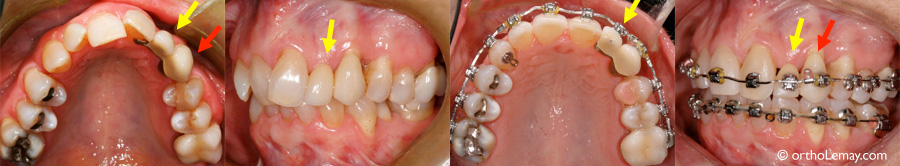

Implant dentaire sur une incisive centrale supérieure (*) posé avant un traitement d”orthodontie.